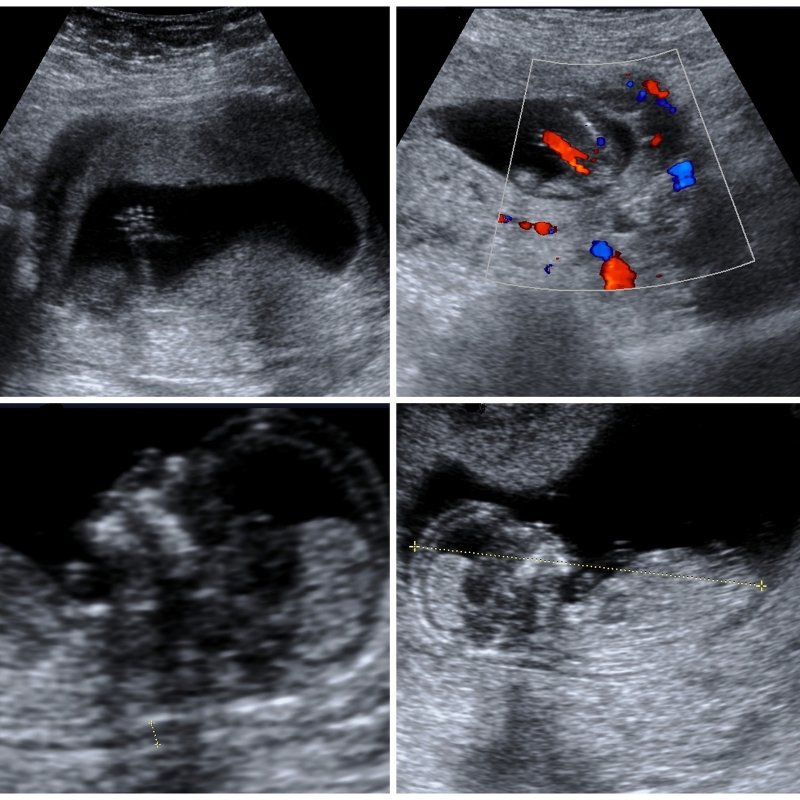

In the second trimester, our foetal morphology ultrasound offers a comprehensive view of your baby’s development. This detailed scan provides a close look at your baby’s anatomy, ensuring healthy growth and identifying any potential anomalies.

Our advanced ultrasound technology allows us to examine your baby’s organs, bones, and other structures in detail. We take great care to ensure all aspects of your baby’s development are thoroughly assessed, giving you peace of mind as you prepare for the next stages of your pregnancy journey.

Our detailed fetal morphology scans provide a comprehensive view of your baby’s anatomy, allowing us to detect potential anomalies and ensure your baby’s healthy development.